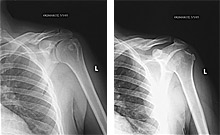

Παραθέτουμε τις ακτινογραφίες.

Η εναπόθεση ασβεστίου φαίνεται καθαρά στις ακτινογραφίες αριστερά, ενώ αυτές δεξιά έχουν ληφθεί μετά την εφαρμογή της θεραπείας όπου το ασβέστωμα έχει εξαλειφθεί.